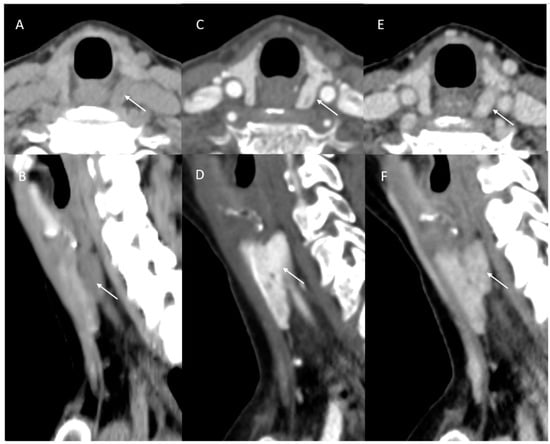

3.4. Incorrect or Incomplete Localization